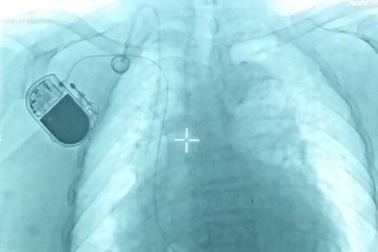

Bệnh viện tuyến quận đầu tiên cấy được máy tạo nhịp timCấy máy tạo nhịp tim vĩnh viễn cho người bệnh là danh mục kỹ thuật phân hạng đặc biệt nhưng đã được Bệnh viện quận Thủ Đức triển khai thành công. Đây được xem là bước tiến quan trọng, nâng chất lượng điều trị ở bệnh viện tuyến cơ sở.

Đặt máy tạo nhịp tim thành công cho bệnh nhân suy thận mãn giai đoạn cuốiNhập viện trong tình trạng ngất liên tục, bệnh nhân được chẩn đoán bị rối loạn nhịp tim, nguy cơ tử vong cao nhưng quá trình chạy thận khiến mạch máu bị biến dạng rất khó đặt máy tạo nhịp tim.

Đặt máy tạo nhịp tim cứu người đàn ông thoát nguy cơ đột tửÔng L.V.Minh (62 tuổi, Hà Nội), có nhịp tim chậm 45 lần/phút, vừa được các bác sĩ Bệnh viện Hồng Ngọc can thiệp đặt máy tạo nhịp thành công, tránh nguy cơ đột tử. Ông chỉ vô tình phát hiện mình bị bệnh tim khi đi khám sức khỏe định kỳ.